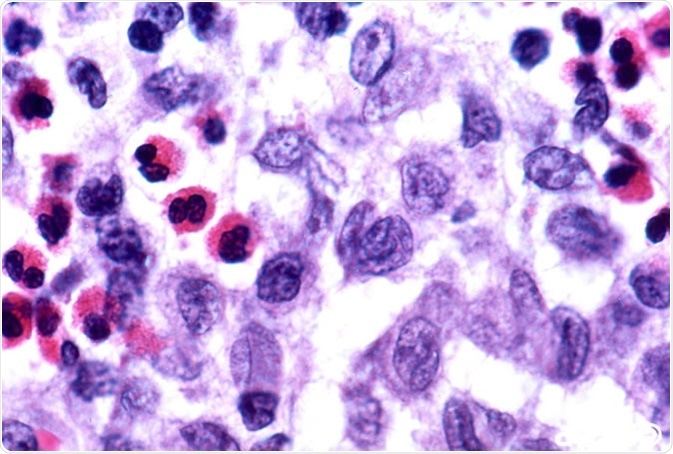

"Langerhans cell histiocytosis" by Pulmonary Pathology is licensed under CC BY-SA 2.0